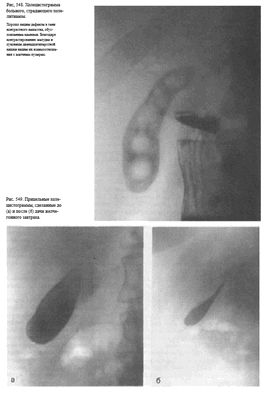

Укладка больного для выполнения снимка. Больной лежит на левом боку. Руки вытянуты кверху и заложены за голову. Кассета размером ЗОХ40 см длинным ребром упирается в поверхность стола и прилежит к пояснице. Верхний край ее соответствует VIII грудному позвонку. Центральный пучок рентгеновского излучения направляют в центр кассеты, на 2—3 см выше срединной линии (рис. 542).

Информативность снимке. На латерограмме отображаются преимущественно правая половина живота и расположенные здесь органы. Особенно отчетливо при этом виден свободный газ в брюшной полости (рис. 543).

Холецистография — методика рентгенологического исследования желчного пузыря, основанная на способности печеночных клеток поглощать из крови некоторые йодсодержащие вещества и выделять их с желчью в желчный пузырь, который обладает способностью концентрировать свое содержимое. Показанием к холецистографии является подозрение на вляют путем однократного (за 14—15 ч) или фракционного (метод насыщения) приема внутрь ди- или трийодированных контрастных веществ (билитраст, билиграфин, йопагност, холевид) и последующей рентгенографии в положении больного стоя за экраном и лежа на животе.

Рекомендуется делать 4 снимка: два — в прямой передней проекции в положении больного стоя (один — без компрессии, второй — с компрессией), третий снимок также в положении больного стоя в левой косой проекции и последний — в положении больного лежа на спине. Первые три снимка обычно выполняют за экраном рентгеновского аппарата под контролем просвечивания, последний — на снимочном столе (рис. 546). Кассету размером 24X30 см устанавливают под правую половину живота с таким расчетом, чтобы центр ее находился на середине расстояния между нижними ребрами и гребнем правой подвздошной кости.

У здоровых людей на холецистограммах определяется интенсивная однородная тень желчного пузыря с четкими контурами (рис. 547).

При калькулезных холециститах тень пузыря менее интенсивна, в проекции пузыря определяются дефекты наполнения, образованные камнями(рис. 548).

Для оценки сократительной и эвакуационной функции желчного пузыря после выполнения снимков (при наличии на них отображения тени желчного пузыря) больному дают желчегонный завтрак (сырые желтки, сливочное масло, сорбит) и спустя 20 и 50 мин делают прицельные снимки (рис. 549).